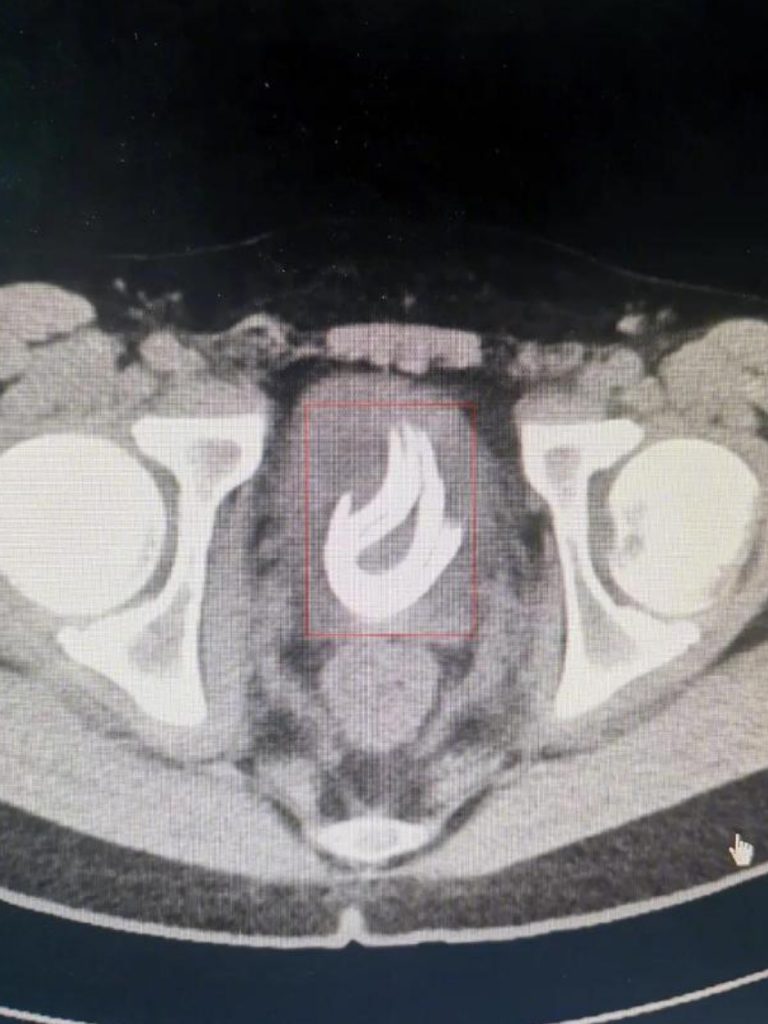

例如:有一位13岁小男孩一直好奇尿液从哪里来,到哪里去,于是,他便将将一根长达70公分的电线塞进尿道里,由于尿道的收缩功能导致电线滞留体内长达3个月之久,直到孩子尿血不舒服才告诉父母。(来源:今日头条)

▲ 图片来源:今日头条。